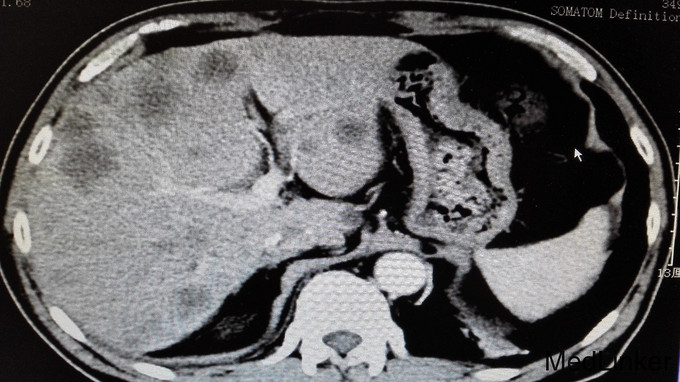

体格检查无特殊,未见明显阳性体征。 进一步完善辅助检查: 尿常规、大便常规、胸片、肝肾功能、血糖、血沉、风湿三项大致正常。血常规:白细胞11.7 ×10 9/L。右小腿MRI:1、右踝周围软组织信号改变,考虑炎症,请结合临床,必要时增强检查。2、右踝关节腔少许积液。血常规、心肌酶、电解质正常,心电图、心脏彩超未见明显异常。腹部CT平扫:1、肝实质多发稍低密度影性质待定,考虑转移瘤,建议进一步检查。2、肝左叶、尾叶多发低密度影性质待定,考虑囊肿。3、胆囊摘除术后。4、主动脉及右冠状动脉局部管壁钙化。AFP、CA199正常,CEA:6256.85ng/ml。输血前四项全阴性。全腹部增强CT提示:1、胃窦壁增厚,肝实质多发稍低密度影,考虑胃CA并肝内转移瘤可能,建议胃镜检查。2、肝左叶、尾叶多发囊肿。3、胆囊摘除术后。4、左肾囊肿。5、右肺下叶感染;左肺下叶纤维化病灶。6、主动脉及右冠状动脉局部管壁钙化。行胃肠镜检查提示慢性浅表性胃炎和盲肠占位,占位大小约40mm,已取病检。病检结果提示:盲肠中分化腺癌。

诊断:1、盲肠中分化腺癌并肝脏多发转移;2、右小腿软组织感染。 告知患者病情,目前无手术治疗指征,转肿瘤科行以化疗为主的肿瘤综合治疗。 患者经过再三考虑后,转省肿瘤医院消化肿瘤内科继续治疗。